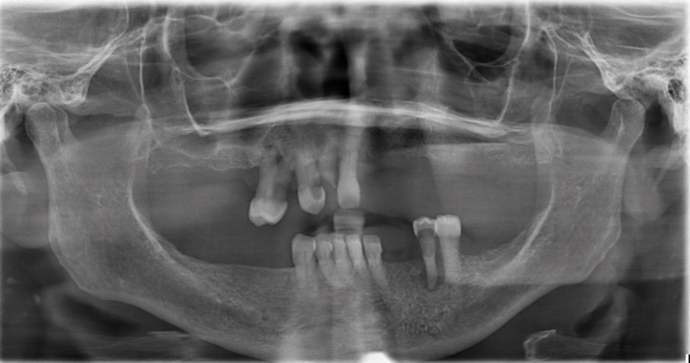

Patient had severe gum disease and she started losing her teeth one by one and was very unhappy with her partials. Patient was holding on to the very last few teeth in her mouth which were loose, in order to avoid wearing dentures! When she discovered Dr Bidra, and was informed that she could get transformed in one single day, she and her husband were immediately motivated. Patient had her teeth extracted, implants placed and new teeth installed all in one day.

Procedures : extractions, implants, All on 4 , Teeth in a day, no bone grafting and full mouth reconstruction with monolithic zirconia bridges.